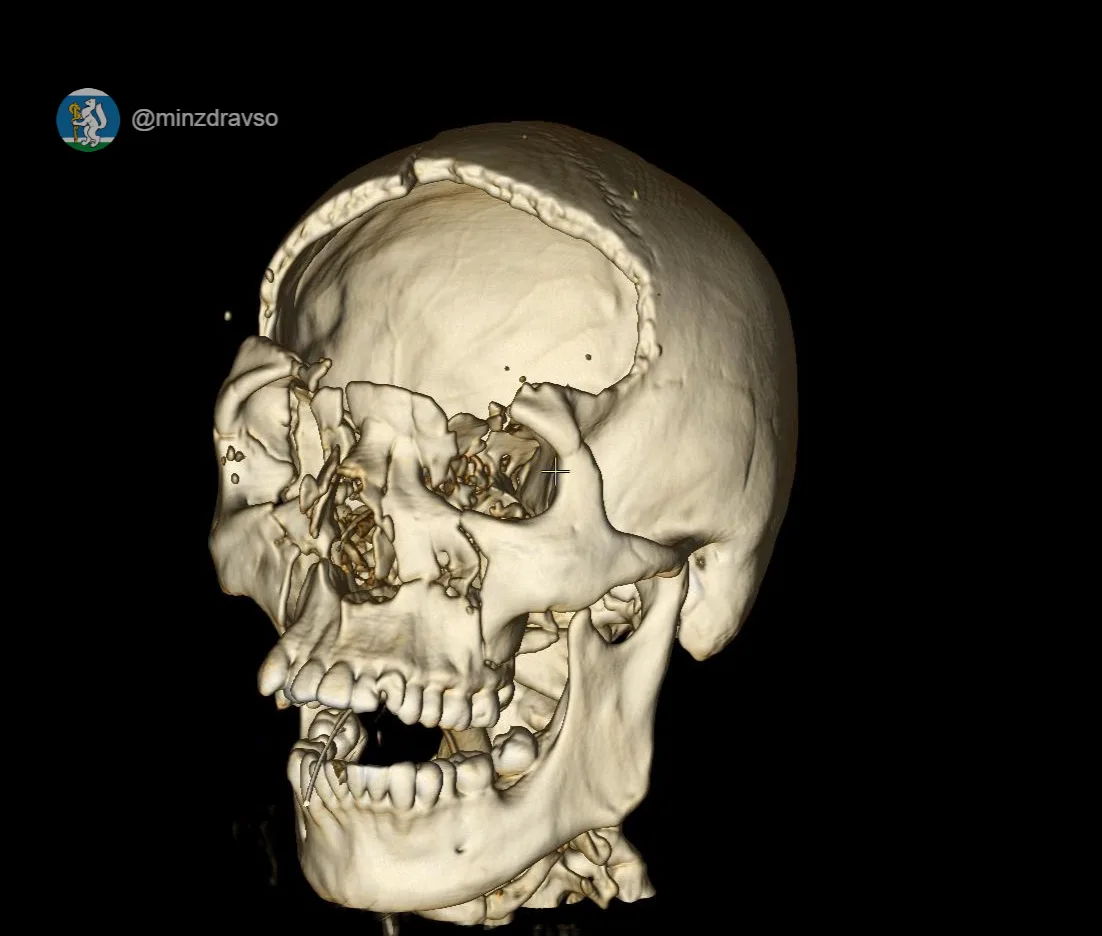

Татьяна Савинова: «Десять месяцев — и маленькая пациентка снова танцует»

Знаете, есть истории, которые напоминают: медицина — это не только диагнозы и протоколы. Это вера. Вера врачей в пациента. Вера родителей в чудо. И вера ребёнка в то, что боль не навсегда.

Вот Алиса. Обычная девочка: школа, друзья, мечты. И вдруг в 11 лет — тяжёлая травма позвоночника. Перелом.

Сегодня рада сообщить, что спустя 10 месяцев юная жительница Режа успешно прошла финальный этап долгого и сложного лечения — операцию по удалению импланта.

Благодаря слаженной работе команды врачей-травматологов и нейрохирургов Уральского института травматологии и ортопедии им. В.Д. Чаклина, невероятной силе духа юной пациентки и поддержке родителей жизнь девочки снова полна радости.

Несмотря на ограничения после операции и длительное ношение шейного корсета, который разрешили снять только в феврале 2026 года после полного сращения позвонков, Алиса продолжила заниматься в хореографической школе, чтобы быть в форме и не отстать от своих сверстниц. Родители поддерживали дочь на каждом этапе, и эта помощь стала неотъемлемой частью пути к выздоровлению.

Недавняя операция по удалению металлоконструкций — завершающий аккорд в этой непростой истории. В знак признательности Алиса приготовила творческую композицию для своего лечащего врача, нейрохирурга Антона Пьянкова. Сувенир стал для доктора сюрпризом и лучшей наградой за труд.